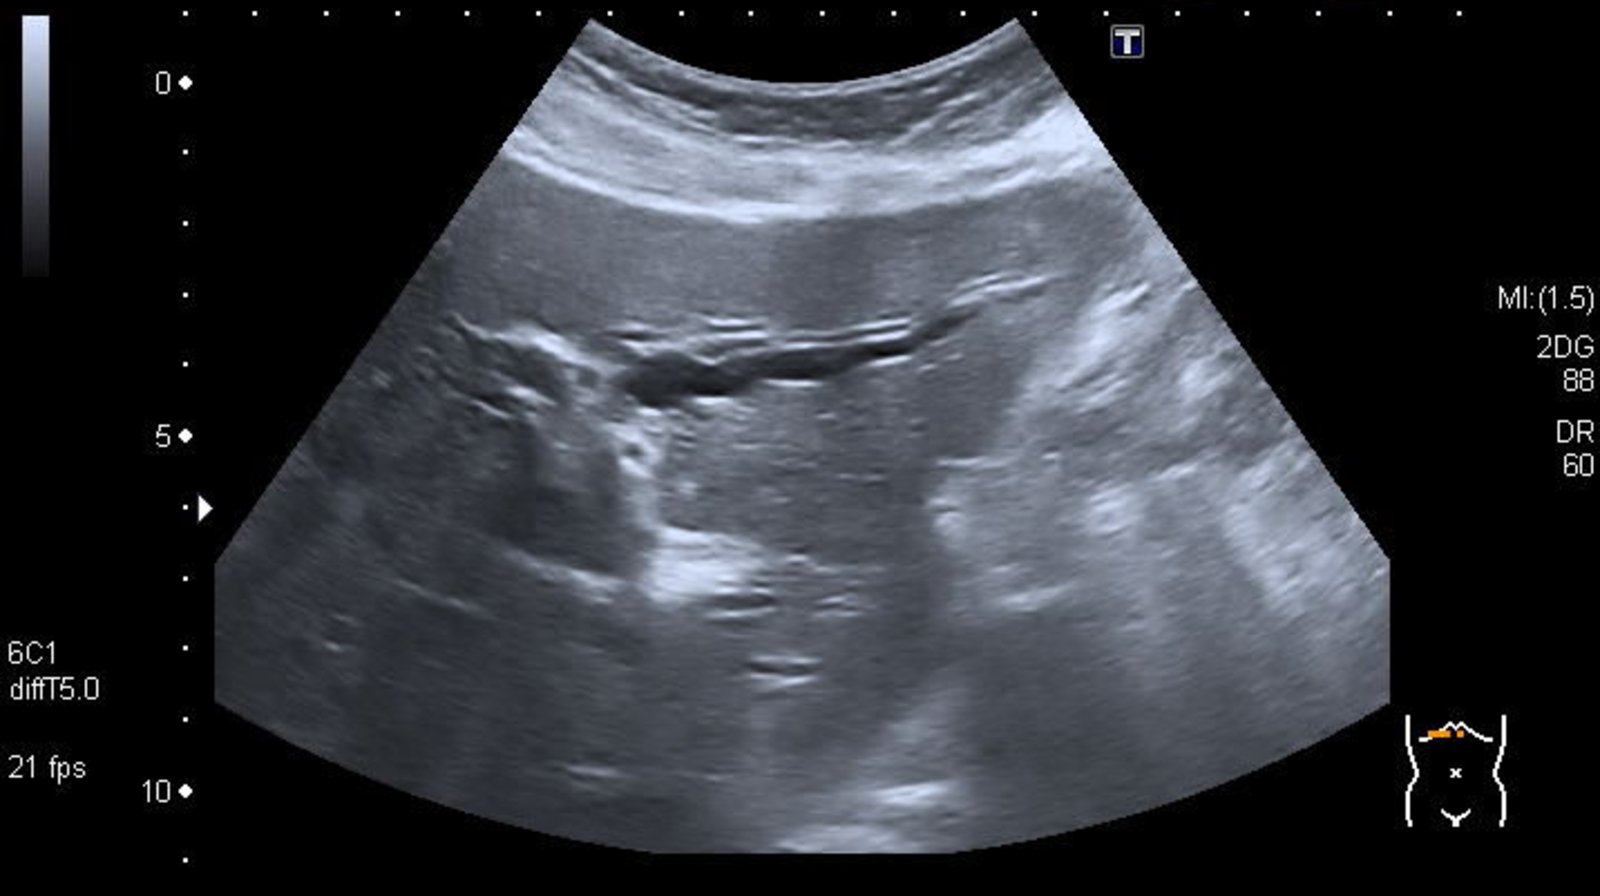

RUQultrasound

• Indication: : preferred first-line imaging modality in patients presenting with suspected cholangitis [8][11][12]

• Supportive findings

• Dilated common bile duct: See ''Diagnosis of choledocholithiasis” for details.

• Dilated intrahepatic bile ducts: indicates obstructive cholestasis

• Thickened bile duct walls [13]

• Evidence of underlying etiology, such as:

• Choledocholithiasis: occluding CBD stone with/without cholelithiasis may be visualized [14]

• Biliary stricture: focal narrowing of the bile duct(s), with dilation of the proximal biliary tree

• Biliary tumor: intraluminal mass within the bile duct

RUQultrasound is not sufficiently sensitive to definitively rule out biliary obstruction. Obtain cross-sectional imaging (i.e., CT abdomen or MRCP) in patients with a high pretest probability of acute cholangitis and a negative RUQultrasound. [8]